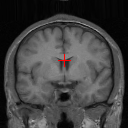

(l) 0.9345

Figure 8 exemplifies the methods on three pairs of scans. Comparison between our methods and traditional methods proves the applicability of our methods to 3D brain registration. Comparison between ADD and DD shows that integrating affine registration subnetwork is effective.